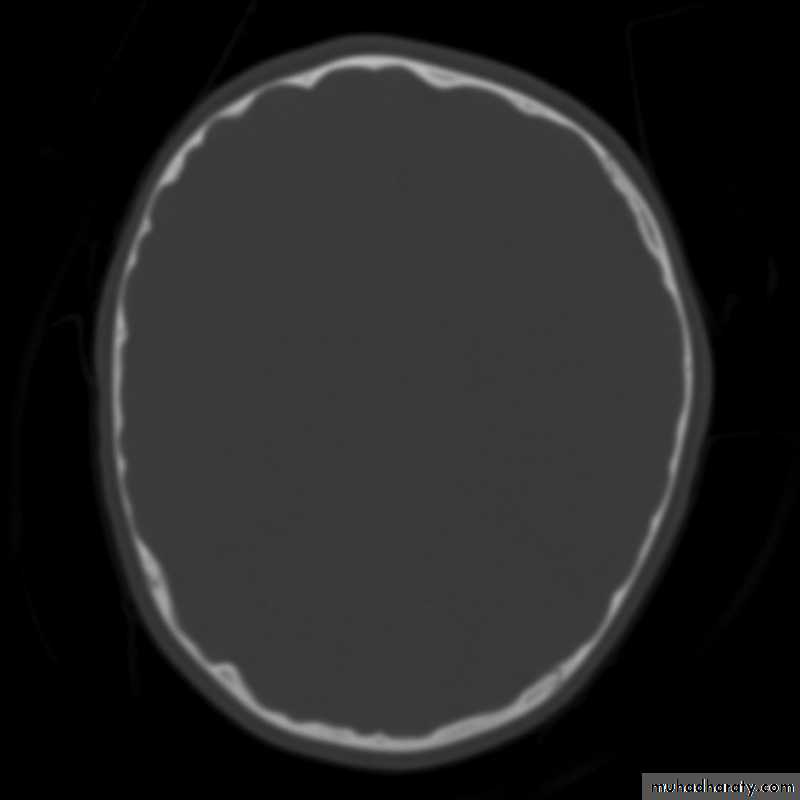

• Sutural separation in children.• ‘Copper-beating’ marking of the cranial vault.

Copper-beating’ marking